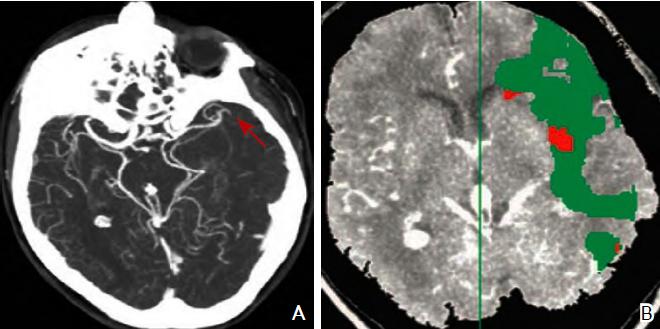

CT灌注成像对于梗死核心灶标记为CBV降低的区域,CBF与MT T以低于界定的阈值(CBV<2 ml/100 g、CBF<20 ml/100 g/min及MTT>8 s)来显示脑的异常灌注区。缺血半暗带为脑梗死核心区与异常灌注区域之间的差异区域(图3)。

图3 CT血管造影(A)及CT灌注成像(B)注:A:CT血管造影显示大脑中动脉闭塞(红色箭头所示);B:CT灌注成像,绿色区域为平均通过时间(MTT)异常区域(MTT 145%,与对侧正常比较),红色区域为脑血容量(CBV)降低区域(CBV<2.0 ml/100 g)。CT:计算机断层扫描